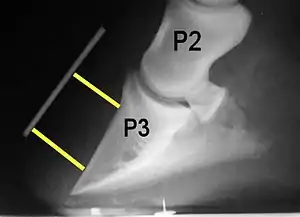

Rotation, sinking, and founder

Normally, the front of the third phalanx is parallel to the hoof wall and its lower surface should be roughly parallel to the ground surface. A single severe laminitic episode or repeated, less severe episodes can, depending upon the degree of separation of dermal and epidermal laminae, lead to either rotation or sinking of the pedal bone, both of which result in anatomical changes in the position of the coffin bone with visible separation of the laminae, colloquially known as founder. Rotation and distal displacement may occur in the same horse.[4] Both forms of displacement may lead to the coffin bone penetrating the sole. Penetration of the sole is not inherently fatal; many horses have been returned to service by aggressive treatment by a veterinarian and farrier, but the treatment is time-consuming, difficult and expensive.

Rotation is the most common form of displacement, and, in this case, the tip of the coffin bone rotates downward.[4] The degree of rotation may be influenced by the severity of the initial attack and the time of initiation and aggressiveness of treatment. A combination of forces (e.g. the tension of the deep digital flexor tendon and the weight of the horse) result in the deep digital flexor tendon literally pulling the dorsal face of the coffin bone away from the inside of the hoof wall, which allows the coffin bone to rotate. Also, ligaments attaching the collateral cartilages to the digit, primarily in the palmar portion of the foot, possibly contribute to a difference in support from front to back. The body weight of the animal probably contributes to rotation of the coffin bone. Rotation results in an obvious misalignment between PII (the short pastern bone) and PIII (the coffin bone). If rotation of the third phalanx continues, its tip can eventually penetrate the sole of the foot.

Radiographs

Radiographs are an important part of evaluating the laminitic horse. They not only allow the practitioner to determine the severity of the episode, which does not always correlate with degree of pain,[1] but also to gauge improvement and response to treatment. Several measurements are made to predict severity. Additionally, radiographs also allow the visualization and evaluation of the hoof capsule, and can help detect the presence of a lamellar wedge or seromas.[1] The lateral view provides the majority of the information regarding degree of rotation, sole depth, dorsal hoof wall thickness, and vertical deviation.[1][17] A 65-degree dorsopalmar view is useful in the case of chronic laminitis to evaluate the rim of the coffin bone for pathology.[1]

Several radiographic measurements, made on the lateral view, allow for objective evaluation of the episode.